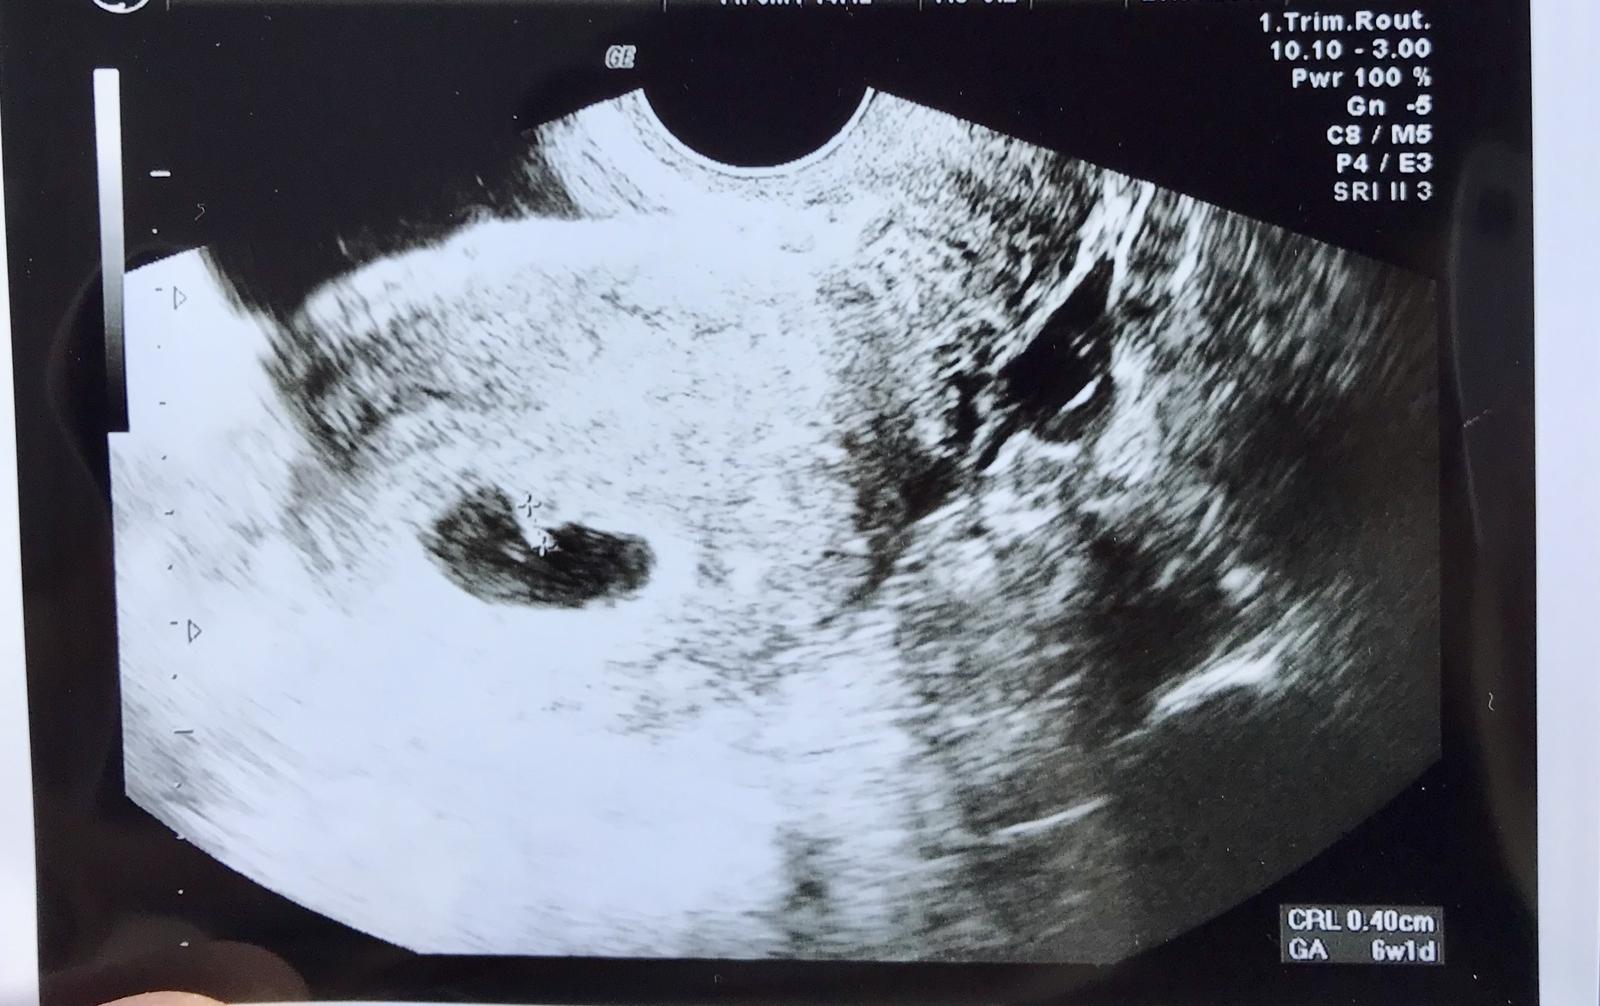

@zuzsat som v 6tt ale áno je to úžasný pocit, plakala som celu cestu domov od šťastia ☺️

Baby 6tt, srdiečko bije 😍😍😍😍